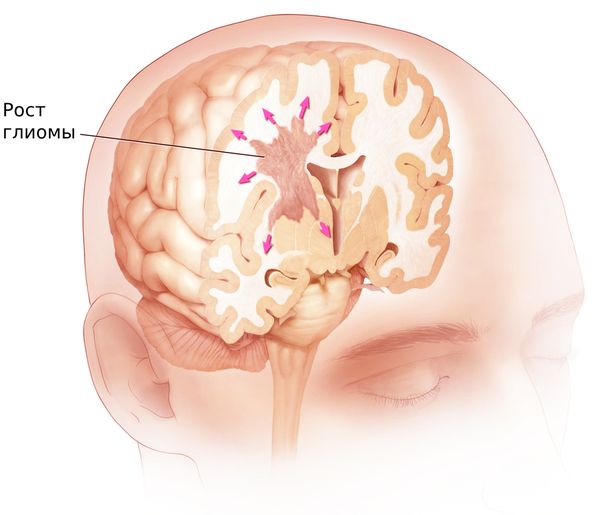

Медицинские аспекты и диагностика субдуральной гигромы мозга